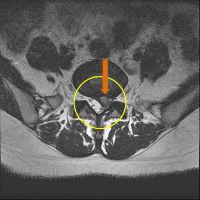

MRI

㸮 ٸ ߰

㸮 ְ , ٱ ־.